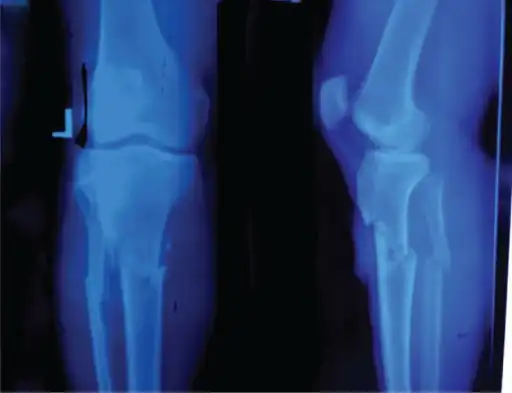

- Knee showing tibial tuberosity avulsion fracture (and proximal tibial fracture)

- X-ray of a 15-year-old male, showing an older avulsion fracture of the tibial tuberosity.